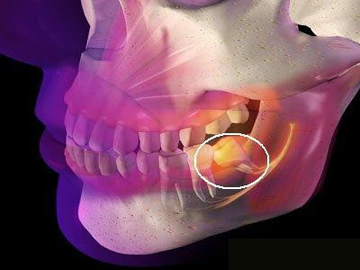

智齒是口腔中的第三大臼齒,有時(shí)候由于各種原因需要拔除,拔智齒是一項(xiàng)復(fù)雜的手術(shù),需要專業(yè)的牙醫(yī)進(jìn)行操作,許多人在考慮拔智齒時(shí),最關(guān)心的問題之一就是拔智齒要花多少錢,本文將詳細(xì)解析拔智齒的費(fèi)用及相關(guān)因素。

1、智齒位置:智齒的位置是影響拔除費(fèi)用的重要因素之一,智齒的位置越深,手術(shù)難度越大,拔除費(fèi)用也就越高。

2、手術(shù)復(fù)雜性:拔智齒手術(shù)的復(fù)雜性也會(huì)影響費(fèi)用,如果智齒生長(zhǎng)位置正常,手術(shù)相對(duì)簡(jiǎn)單;如果智齒被埋在骨頭里,需要切開牙齦和骨頭,手術(shù)難度增大,費(fèi)用相應(yīng)增加。